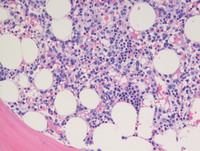

Figure 3: Bone marrow biopsy H&E

Core biopsy is normocellular as evident on low power (Top left image). High power images demonstrate increased number of large mononuclear cells with fine chromatin and prominent nucleoli, compatible with blasts (Black arrow-Top right image). Islands of erythroid precursors are also noted. Megakaryocytes are decreased and occasional micromegakaryocytes with separated nuclear lobes or a single nuclear lobe are identified (White arrow-Bottom image). Reticulin stain showed mild fibrosis.